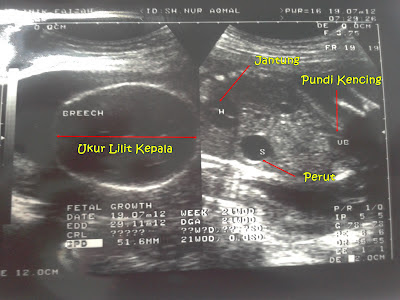

Pastu Doktor check mulut Wafiy, mulut Wafiy ok. Tapi tak nampak lagilah muka Wafiy sebab bukan scan 4D. Kemudian, Doktor check tangan & jari Wafiy. Wafiy suka letak tangan kat muka Wafiy, jari Wafiy pun ok. Kemudian Doktor tunjukkan jantung, perut, tali pusat & pundi kencing kat mommy. Jantung Wafiy berdegup kencang & dah ada 4 injap. Yang paling penting Doktor tunjukkan pistol Wafiy kat mommy. Tapi mommy kata mommy lagi suka panggil pisang huhu. Last sekali, Doktor kirakan air ketuban mommy & semuanya ok.

| Scan 5 bulan Wafiy 1 |

| Scan 5 bulan Wafiy 2 |